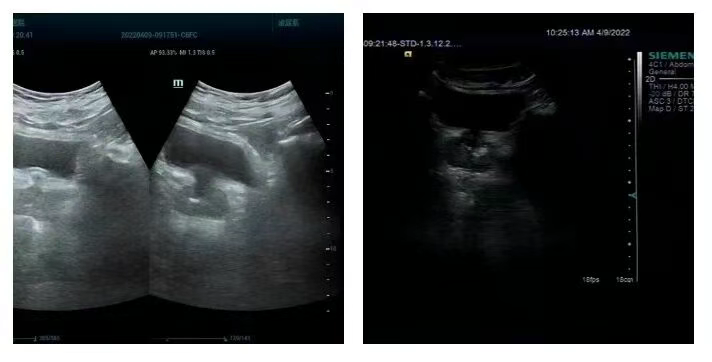

什么是钙化灶?

是指用彩超或CT图像上测到的某器官的出现类似结石一样的强回声或高密度影像的钙质沉淀。常见有肝钙化灶、前列腺钙化灶、肾钙化灶、肺钙化灶等。

钙化灶的形成

钙化灶一般是由炎症和结核引起,如肺结核在治愈后也可形成肺部钙化灶,类似于疤痕。肝内有钙化点可能是肝内胆管壁部分钙化,它的原因多由于炎症、结核等引起,也可能是既往的创伤、出血、脓肿或肉芽肿后形成的“瘢痕”钙化灶。一般病变趋于稳定或愈后,不需要特殊处理。